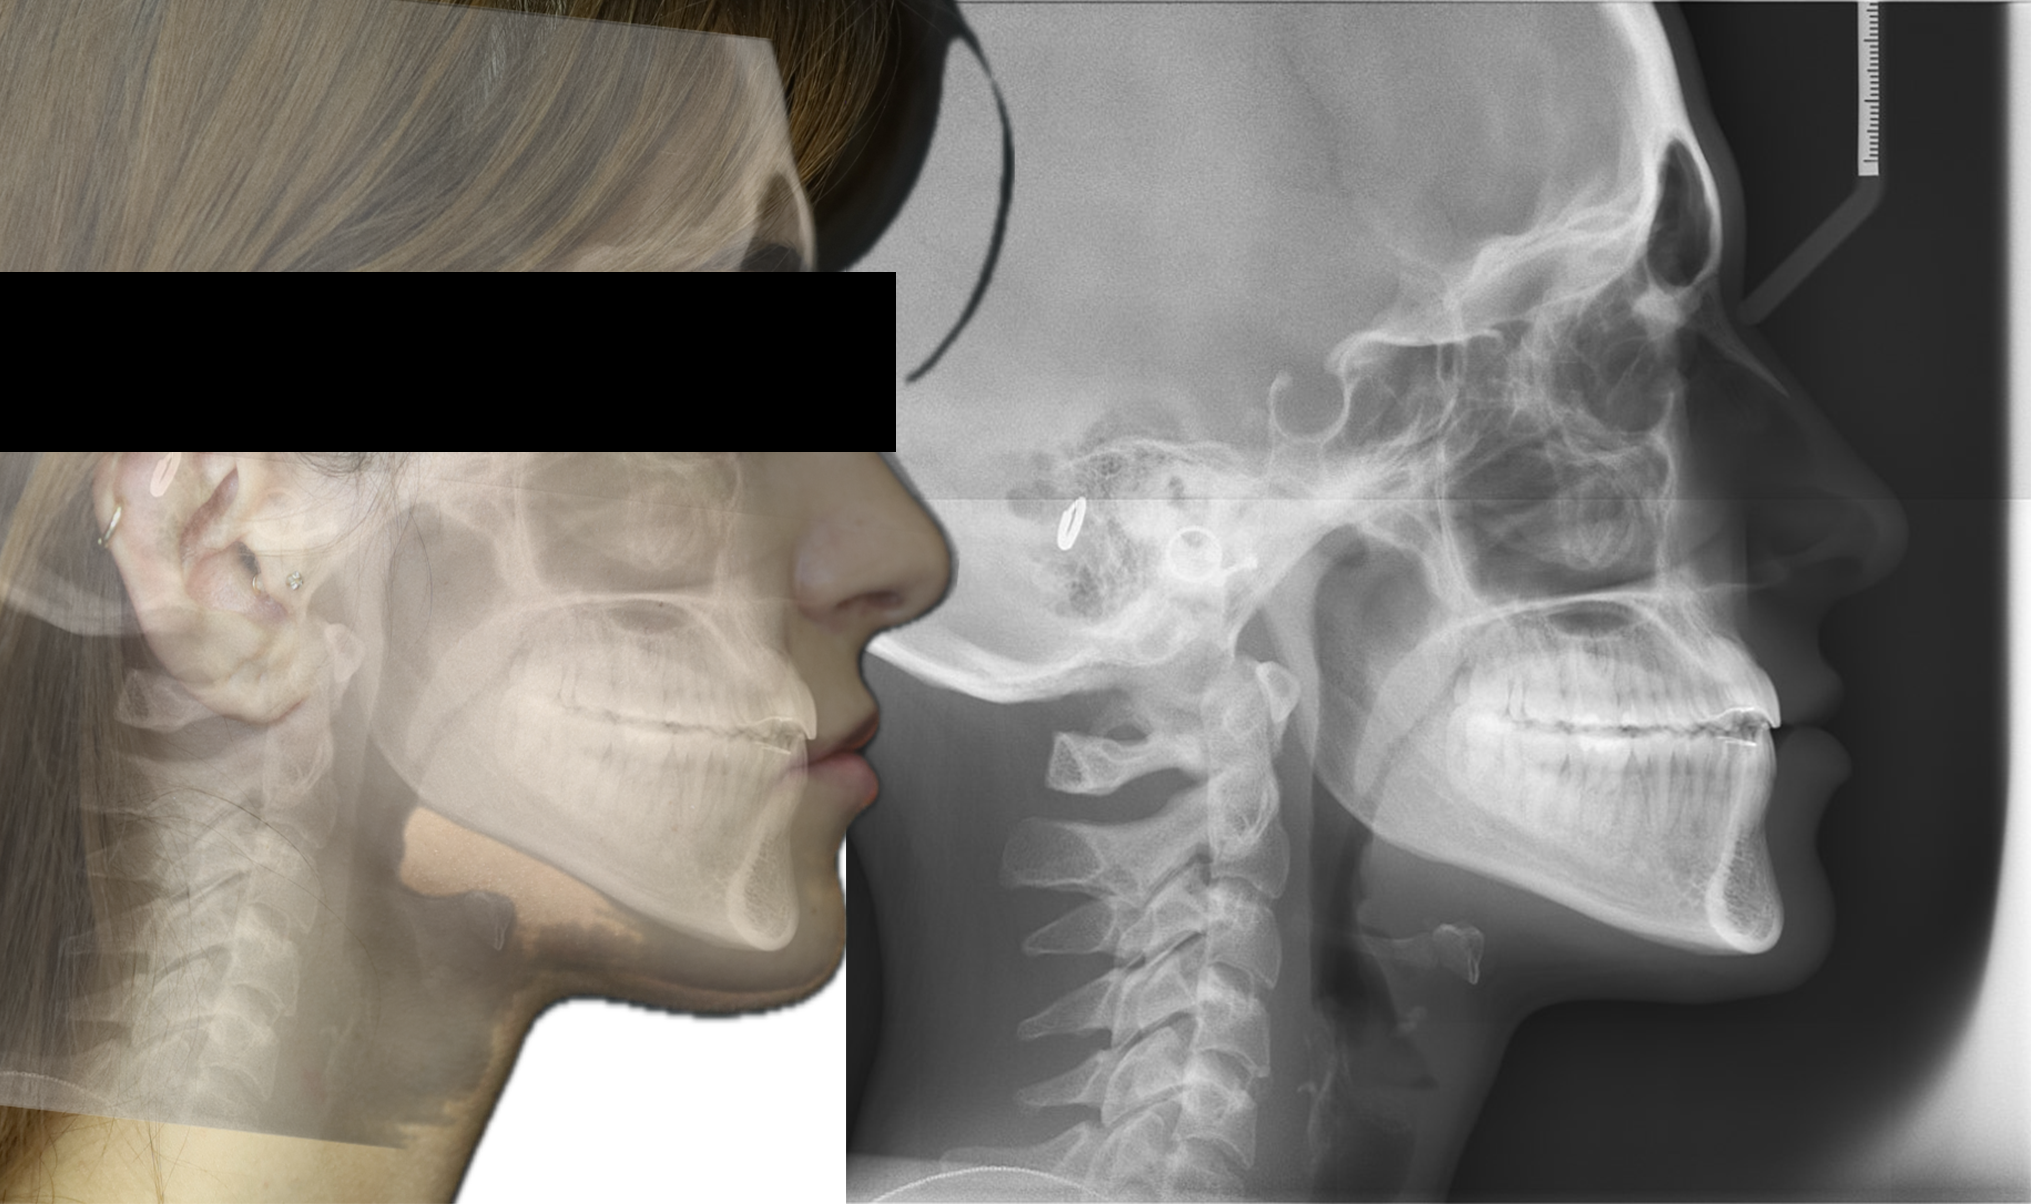

A 22-year-old female patient presented with a Class III malocclusion. She does not like her own profile. Her facial profile was straight with a slightly retrusive maxilla, the upper incisors were within normal inclination, and the lower incisors were retroclined. Bolton discrepency is on mandible for 6 teeth. A retruded upper lip and a normally positioned lower lip were noted. There was also a marked lack of midface support, and the constricted dental arches resulted in a narrow smile and pronounced dark buccal corridors.

At the end of treatment, the patient’s occlusion was corrected to Class I molar and canine relationships with a physiological overjet and overbite. Irregularities in both arches were eliminated, arch forms were coordinated, and incisor torque was effectively controlled to position the roots centrally within the alveolar bone, enhancing stability. Satisfactory intercuspation was achieved in both the anterior and posterior segments, with maintenance of midline coincidence and periodontal health throughout treatment. The case was finished and transitioned into the retention phase using fixed retainers in the maxillary and mandibular anterior regions.